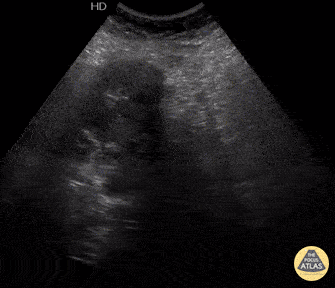

52-yo female presents to ED hypotensive with diffuse urticaria after blunt trauma to abdomen from a fall. FAST exam revealed a small amount of free fluid in RUQ and an abdominal mass. Diagnosis later confirmed to be a ruptured hepatic hydatid cyst. Image courtesy of Robert Jones DO, FACEP @RJonesSonoEM Director, Emergency Ultrasound; MetroHealth Medical Center; Professor, Case Western Reserve Medical School, Cleveland, OH View his original post here